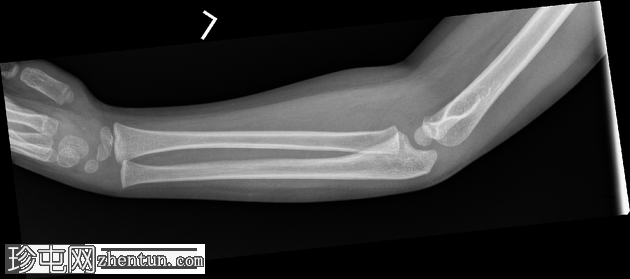

X光片

3.png

正面

在正位片和侧位片上,桡骨近端干骺端可见轻微的皮质断裂和不规则,骨折线似乎向骺端延伸。

相关的脂肪垫征(可见前脂肪垫和帆状征,后脂肪垫阳性)进一步支持骨折后关节内积液的存在。

总体而言,骨性对线保持良好,无脱位迹象。

骨化中心与年龄相符。